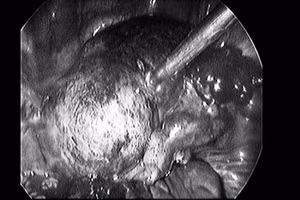

GD&TĐ - Các bác sĩ Bệnh viện Hữu Nghị Lạc Việt ( Vĩnh Phúc ) đã phẫu thuật nội soi khẩn cấp để cứu nữ bệnh nhân trẻ bị U bì buồng trứng (U quái) đang có có dấu hiệu xoắn hoại tử .